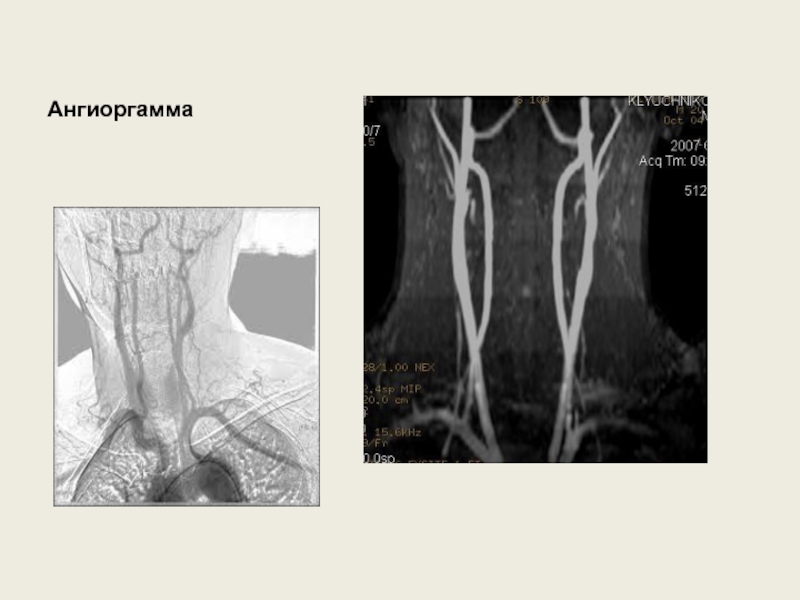

Слайд 31Ангиоргамма

Ангиоргамма